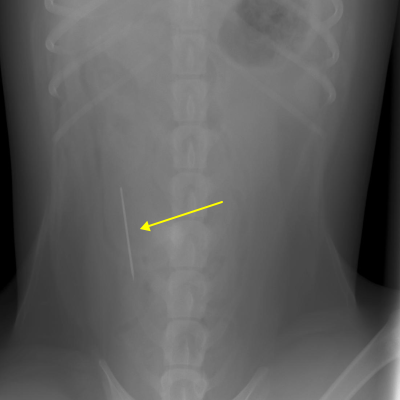

異物の誤飲

犬猫は食べ物ではないものを食べてしまうことがあります。 それは年齢に関係なくおこりますが若い犬猫のほうが多いです。

下の写真は縫い針を飲み込んだ例です。

【症状】

今回は胃や腸管の通過障害をおこすものではありませんでしたが腸にささる可能性がありました。

針はすでに腸に達していますがこの時点での症状はありませんでした。

【治療】

手術で針を摘出するのがよい方法ですが、諸条件を考慮して今回は通過するのを待ちました。

【経過】

一週間後のエックス線検査で針が無事に排出されたことが確認できました。

通常、異物が胃にある場合は嘔吐させることが多いですが、骨や針など先が尖ったものは催吐により食道にささる危険性があるため摘出手術を選択します。

今回のようにうまく排出される場合もありますが、腸に刺さる危険性もあるため通過を待つことがベストな方法ではありません。